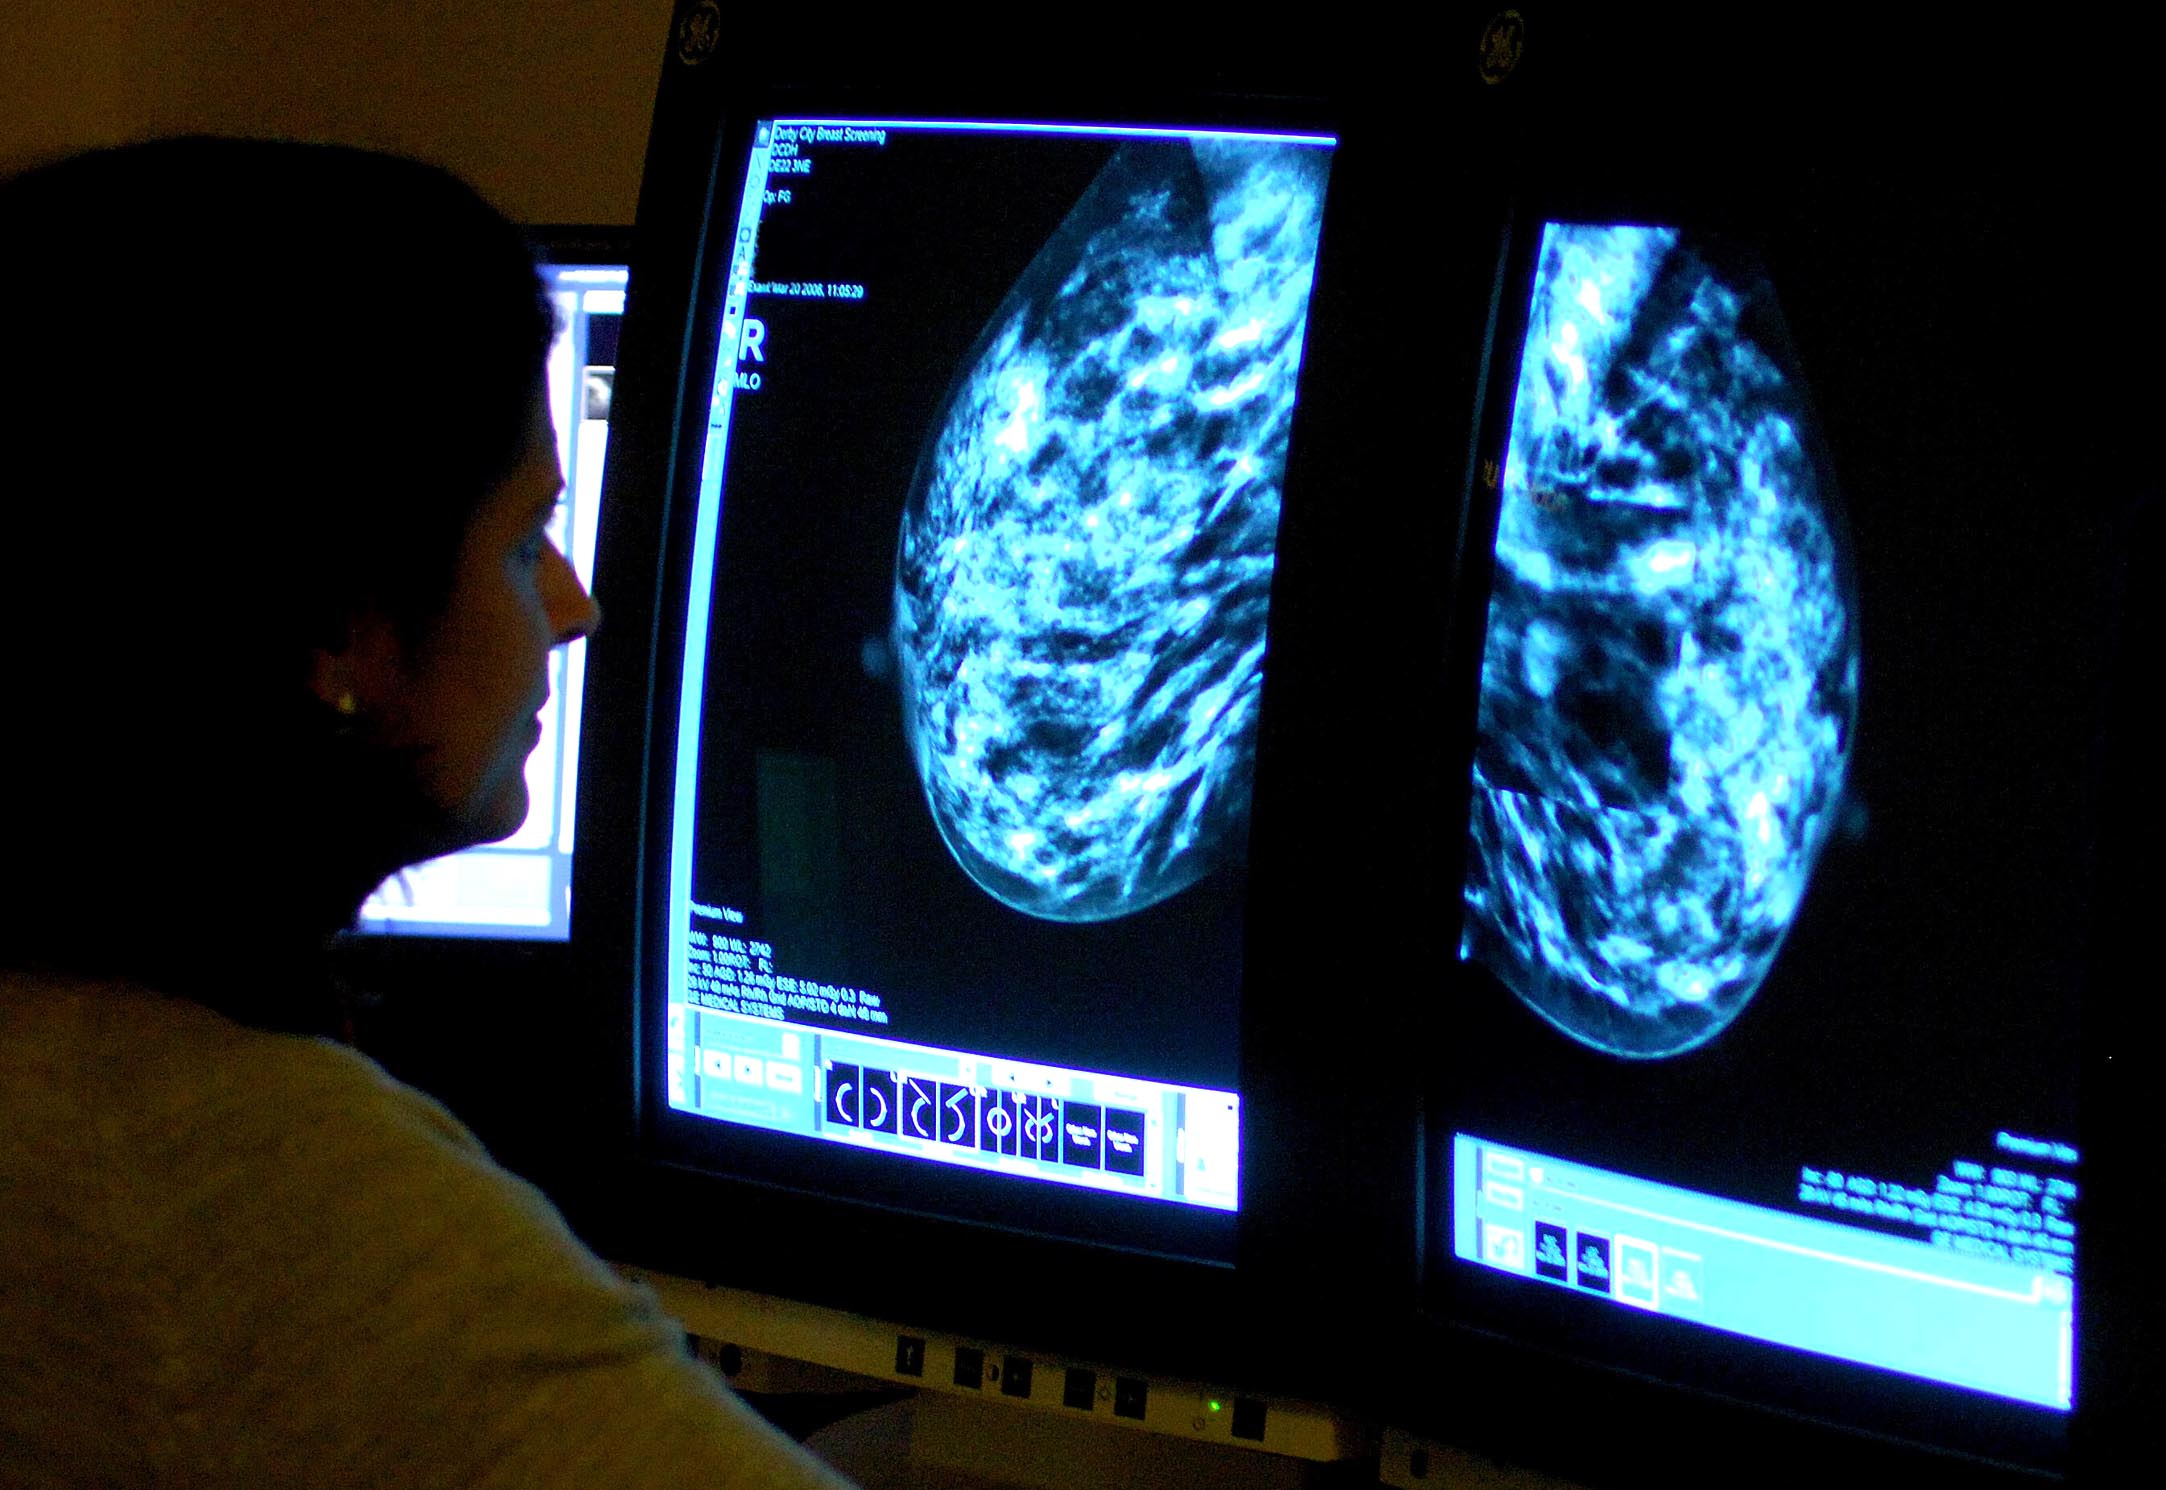

More women in Gloucestershire undergo breast cancer screening – as NHS England target met for first in five years

Breast screening uptake in Gloucestershire remains below pre-pandemic levels